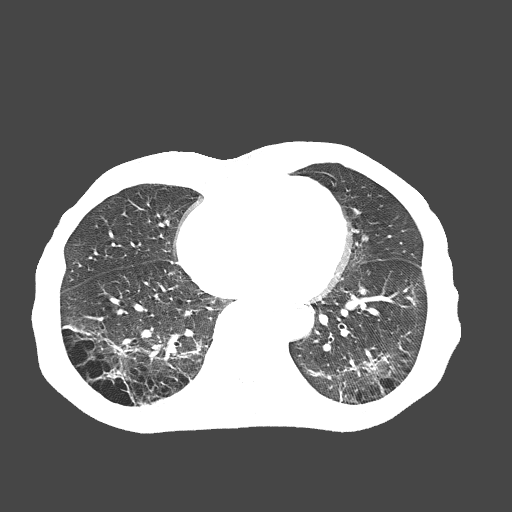

Figure 2: Example chest CT images from the COVIDx-CT dataset, illustrating (a) COVID-19 pneumonia cases, (b) non-COVID-19 pneumonia cases, and (c) normal control cases.

To build the proposed COVIDNet-CT, we constructed a dataset of 104,009 chest CT images across 1,489 patient cases, which we refer to as COVIDx-CT. To generate the COVIDx-CT dataset, we leverage the CT imaging data collected by the CNCB [17], which is comprised of chest CT examinations from different hospital cohorts across China as part of the China Consortium of Chest CT Image Investigation (CC-CCII). More specifically, the CT imaging data consists of chest CT volumes across three different infection types: novel coronavirus pneumonia due to SARS-CoV-2 viral infection (NCP), common pneumonia (CP), and normal controls. Figure 2 shows example CT images for each of the infection types from the constructed COVIDx-CT dataset. For NCP and CP CT volumes, slices marked as containing lung abnormalities were leveraged. Additionally, we excluded CT volumes where the background had been removed to leave segmented lung regions, as the contrast between the background and segmented lung regions can lead to model biases. Finally, we split the COVIDx-CT dataset into training, validation, and test sets, using an approximate 60%-20%-20% split for training, validation, and test, respectively. These sets were constructed such that each patient belongs to a single set. Figure 3 shows the distribution of patient cases and images in the COVIDx-CT dataset amongst the different infection types and dataset splits.